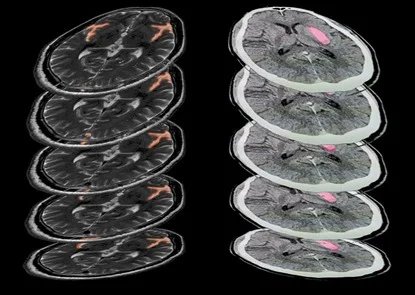

Both image annotation and segmentation services are integral to medical image analysis, contributing to the development of AI-powered tools, clinical decision support systems, and research outcomes.

Outsourcing image annotation services allows organizations to access the expertise of professionals who are well-versed in medical imaging. Image annotation companies often employ radiologists, medical professionals, and imaging experts who have extensive training in medical image analysis. This ensures that the annotated data is of the highest quality, which is essential for AI training, clinical decision-making, and research purposes.

Moreover, outsourcing companies invest heavily in advanced image annotation tools and AI-assisted platforms, which are costly for individual organizations to implement on their own. These tools enhance the accuracy of segmentation and annotation, ensuring precise results that may not be achievable with manual processes.

Medical image annotation and segmentation are crucial to the development of AI-based diagnostic tools and for clinical research. Any mistakes in annotation can lead to inaccurate machine learning models or flawed research findings. Hence, accuracy is paramount.

Reputable image annotation companies adhere to strict quality control measures to ensure that the annotations they provide are accurate and reliable. These companies implement multiple layers of quality checks, including manual reviews and automated validation systems, to minimize the risk of errors. As a result, outsourcing to established companies often results in more accurate and precise annotations compared to relying on in-house teams with less experience or expertise.

Moreover, outsourcing allows for access to specialized tools and technologies that can improve the consistency and accuracy of image annotations, leading to higher-quality data for AI model training, clinical analysis, and research.